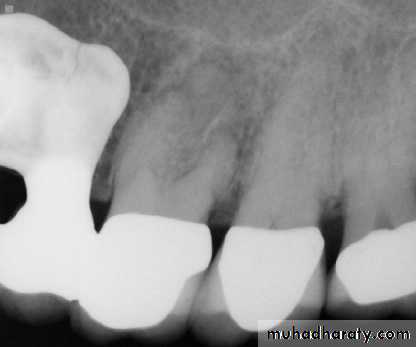

Teeth are composed of pulp (arrow on the secondmolar), enamel (arrow on the first molar), dentin (arrow onthe second premolar), and cementum (usually not visibleradiographically).

Radiographic Anatomy Basics: The Tooth

Radiographic Anatomy Basics